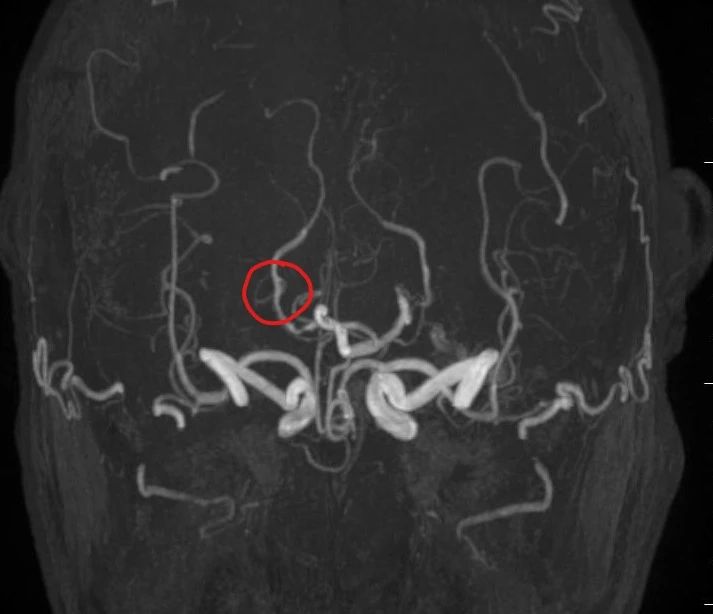

1. 伪影干扰,小血管显示受限。

对重度狭窄、钙化斑块或直径<2mm的小血管,图像可能模糊或出现假阳性(如夸大狭窄程度)。